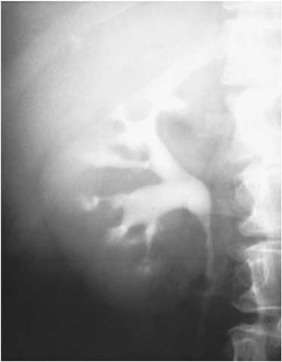

Uno de los métodos más útiles para evaluar la anatomía renal en pacientes con riñón esponjoso medular es la tomografía computarizada (tomografía computarizada, o CT en inglés), la cual permite una visualización detallada de la estructura interna del riñón. En la tomografía computarizada, el hallazgo más distintivo es la dilatación quística de los conductos colectores distales. Estos conductos, que normalmente tienen un tamaño reducido y están organizados de manera regular, presentan una expansión irregular en el contexto del riñón esponjoso medular, lo que se traduce en la formación de pequeños quistes dentro de la médula renal. Esta dilatación quística genera una apariencia característicamente estriada en las imágenes, que resulta de las paredes de los conductos dilatados y las diferentes densidades del tejido renal circundante. Esta estriación, combinada con la presencia de los quistes, es un indicio claro del trastorno.

Además de la dilatación quística, la tomografía computarizada también puede mostrar calcificaciones en el sistema colector renal. Estas calcificaciones son depósitos de calcio que pueden formarse debido a la alteración en la dinámica del flujo urinario y la estasis dentro de los conductos colectores dilatados. La calcificación en los riñones de los pacientes con riñón esponjoso medular se asocia a la presencia de cálculos renales, nefrocalcinosis (depósitos de calcio en el parénquima renal) y a la alteración del metabolismo del calcio que ocurre en esta condición. Las calcificaciones en las imágenes de tomografía computarizada son particularmente útiles para establecer el diagnóstico, ya que proporcionan evidencia directa de la alteración estructural y funcional que caracteriza a esta enfermedad.

El ultrasonido renal también es una herramienta diagnóstica eficaz, especialmente cuando no se dispone de tomografía computarizada. En el ultrasonido, los hallazgos son similares a los de la tomografía computarizada. Se puede observar la dilatación quística de los conductos colectores en la región medular del riñón, aunque con menor detalle que en la tomografía computarizada. La imagen en ultrasonido muestra áreas ecogénicas (más brillantes) que corresponden a las dilataciones quísticas y, en algunos casos, a las calcificaciones, aunque la visualización de estas últimas puede ser menos precisa en comparación con las imágenes obtenidas por tomografía computarizada. Sin embargo, cuando se observan estos hallazgos, especialmente en un contexto clínico compatible con el riñón esponjoso medular, el ultrasonido puede ser suficiente para confirmar el diagnóstico o, al menos, para orientar al médico hacia la sospecha diagnóstica.